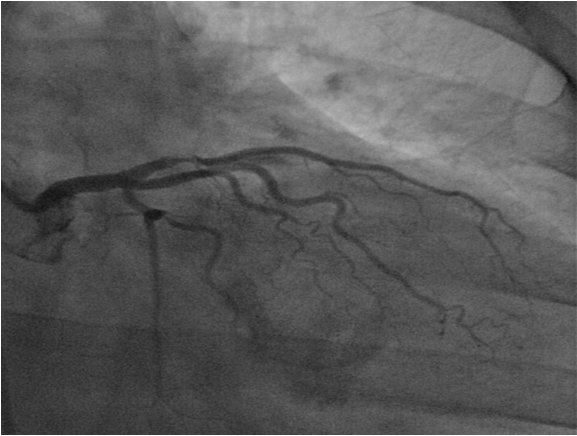

Patient was admitted for serial EKG and troponin follow-up, he was pain free during his hospital stay, and in one of the next EKG about 8 hours after admission biphasic T-waves in V1-V6 was seen (Figure 1) with minimal elevation in the troponin level to 0.10. The patient was taken for cardiac catheterization for further evaluation in light of these changes. Cardiac catheterization showed 99% occlusion of LAD (Figure 2), with grossly patent right coronary artery. He subsequently underwent balloon angioplasty and a drug-eluting stent placement in the proximal portion of the LAD. A follow-up left ventriculogram showed anterior apical wall hypokinesis with left ventricular ejection fraction (LVEF) of 45%.The patient continued to improve clinically and did not have any further episodes of chest pain or any shortness of breath during his hospital course. His follow-up EKG showed resolution of electrical changes from before. He was discharged a day later on aspirin, prasugrel, metoprolol and atorvastatin.

Figure 2: Coronary angiography performed next days after admission, showing a critical stenosis in the proximal part of the left anterior descending coronary artery.